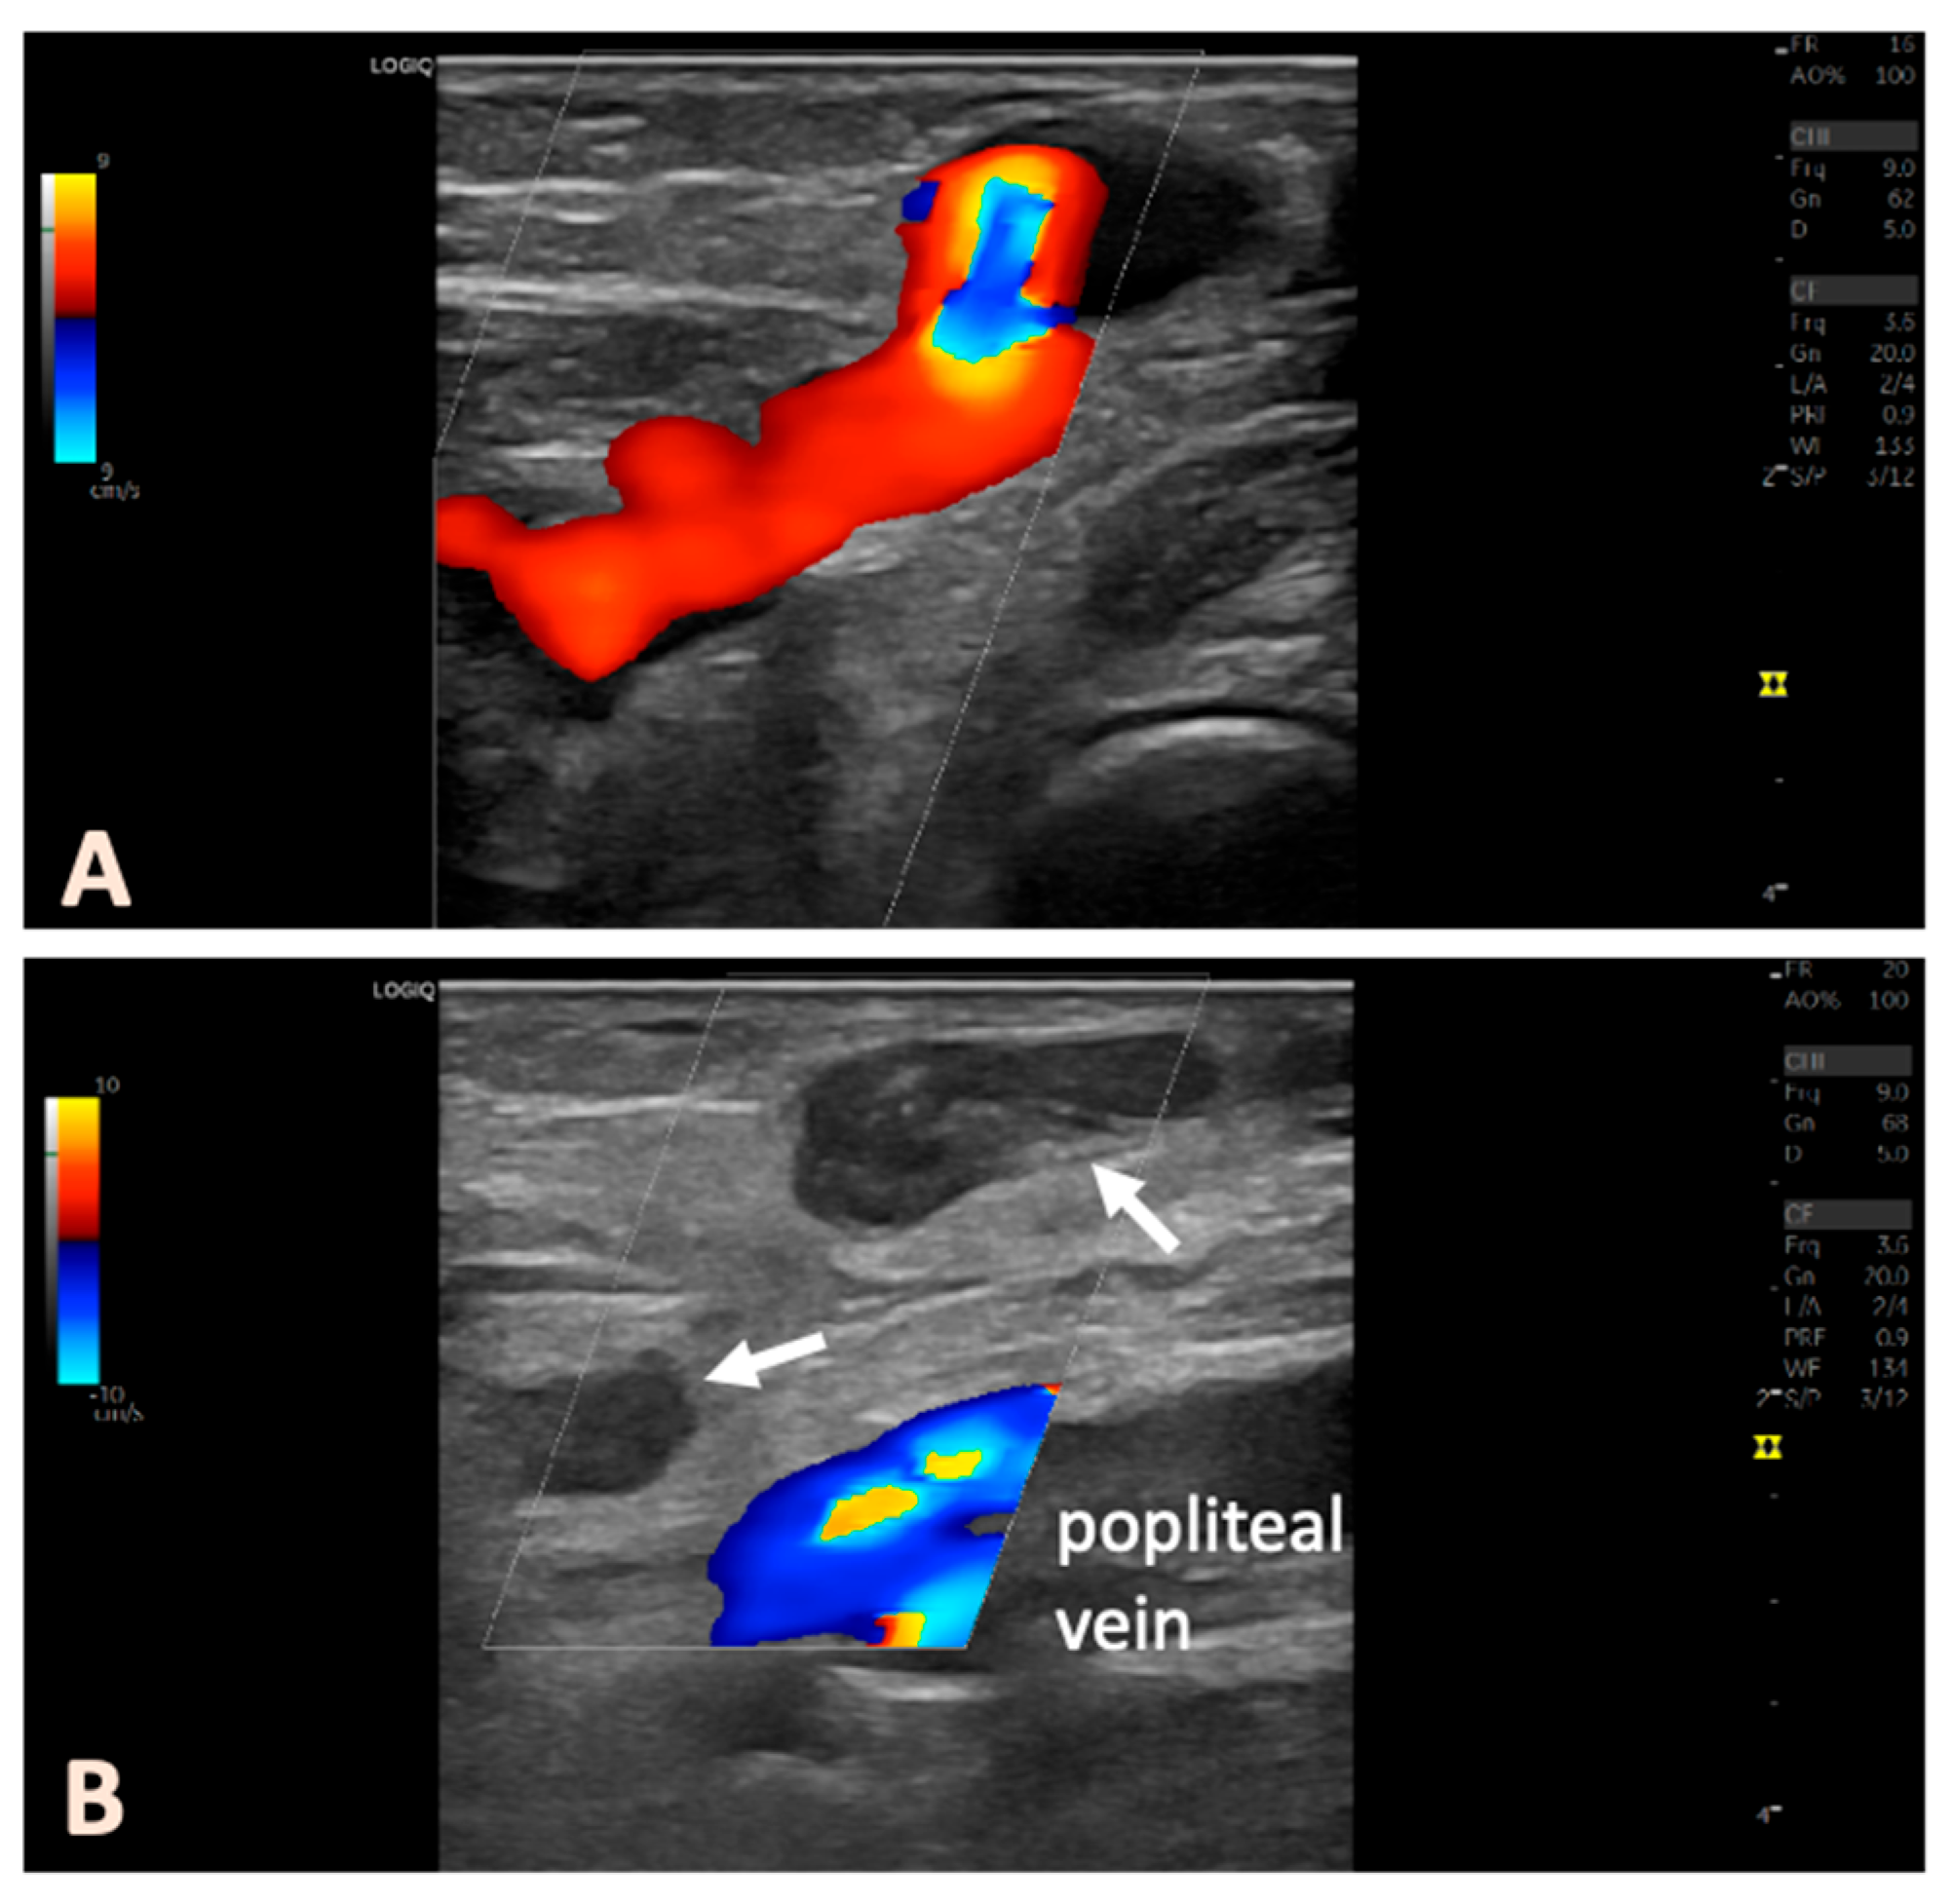

2.4. Postoperative Follow-Up

Figure 2. Pre- and post-interventional duplex ultrasound in an example of a patient with a right-sided PFPV. The ultrasound probe is positioned in a longitudinal orientation. (A) preoperative findings; (B) postinterventional findings, with the thermally treated veins below and above the popliteal fascia occluded (arrows).